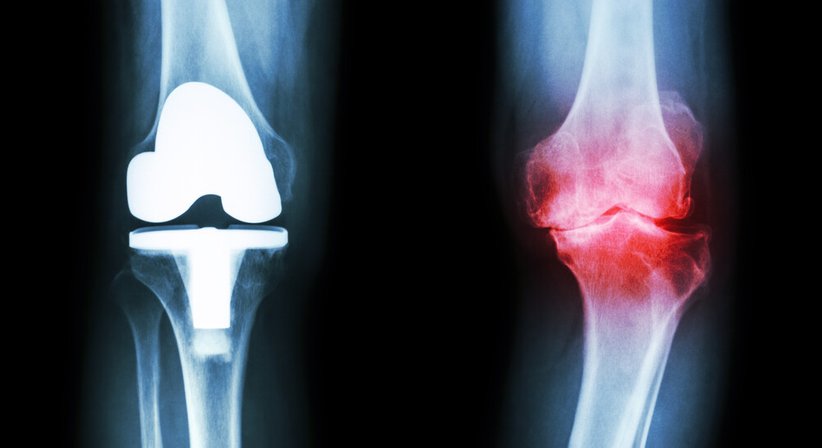

Besteht ab einem bestimmten Zeitpunkt im Krankheitsverlauf jedoch eine massive Arthrose vom Kniegelenk und sind konservative und arthroskopische/gelenkerhaltende Operationsmethoden nicht mehr wirksam, dann sollte die Implantation einer Knieprothese (Kniegelenkersatz, “künstliches Knie“) in Erwägung gezogen werden. Eine Knieprothese ersetzt das abgenützte Kniegelenk und ermöglicht es, Schmerzen und Bewegungseinschränkungen (weitestgehend) zu beseitigen und die Lebensqualität zu verbessern.

Abhängig davon, ob das Kniegelenk teilweise oder ganz ersetzt wird, wird grundsätzlich zwischen der Teilprothese (einseitige Schlittenprothese) und der Total-Endoprothese unterschieden (Knie-TEP). Bei einer Teilprothese wird während der Operation nur ein Teil vom Kniegelenk ersetzt, das restliche Gelenk (die gesunden Anteile) bleibt erhalten. Bei einer Total-Endoprothese wird das gesamte Gelenk durch die Prothese ersetzt. Jeder Prothesen-Typ ist in unterschiedlichen Formen, Größen und Ausführungen verfügbar; welche Prothese zum Einsatz kommt richtet sich nach verschiedenen Faktoren (Alter, Geschlecht, Körperbau, Gesundheitszustand, Knochenqualität, körperliche Aktivität etc.).